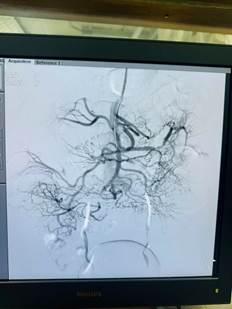

Động mạch mạc treo tràng trên được can thiệp tái thông

Hình 2: Động mạch mạc treo tràng trên được can thiệp tái thông

Ngay lập tức, cuộc hội chẩn liên khoa giữa khoa Ngoại Tổng hợp, Hồi sức tích cực – chống độc, Chẩn đoán hình ảnh và đơn vị Tim mạch can thiệp được diễn ra, các bác sĩ xác định tình trạng thiếu máu ruột của bệnh nhân chưa dẫn đến hoại tử ruột (chưa có phản ứng thành bụng, dấu hiệu nhiễm trùng nhiễm độc chưa rầm rộ, chưa có dấu hiệu hoại tử ruột trên phim cắt lớp vi tính) và đi đến thống nhất chỉ định can thiệp lấy huyết khối động mạch mạc treo dưới số hóa xóa nền. Bệnh nhân được chuyển vào phòng tim mạch can thiệp, các bác sĩ tiến hành chụp và can thiệp hút ra rất nhiều huyết khối, tái thông động mạch mạc treo tràng trên.